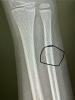

Называется не ходили в поликлиники по ОМС, и не стоило начинать. Ремонты красивые сделали, улыбающихся девочек поставили на входе, а врачи на от**бись работают. Мой бедный ребенок проходил со сломанной рукой НЕДЕЛЮ. Потому что в травмпункте не увидели перелом. Вчера поехали, сделали рентген платно и я своими глазами видела сломанную кость. Как врач мог этого не увидеть не понимаю. Так сынуля получил гипс на свой день рождения.

А где на фото перелом?